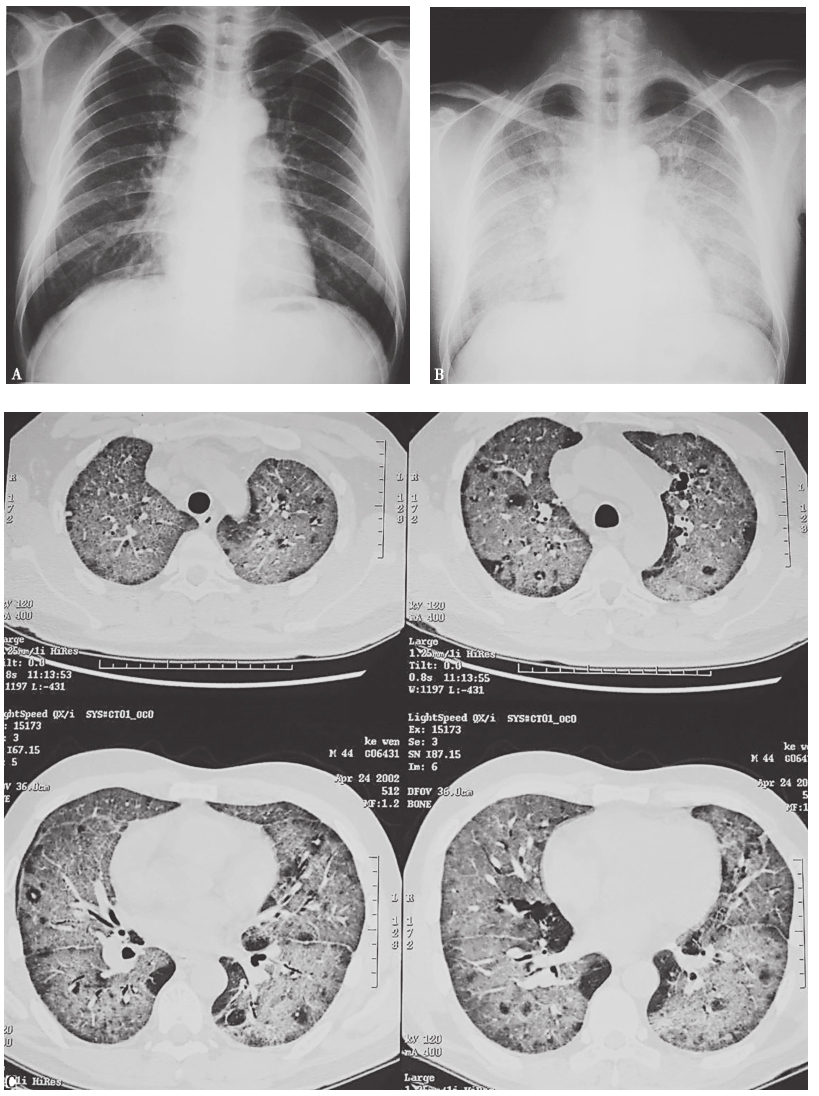

图5 肺淋巴瘤胸部影像学表现

男性患者,44岁,间断发热9个月,痰中带血1个月。胸部X线片(A)可见右中上纵隔旁肺野大片高密度影,CT(B)可见右上叶前段和中叶大片实变影,并见支气管充气征。病理诊断为肺淋巴瘤

图6 肺鳞癌胸部影像学表现

女性患者,86岁,痰中带血5个月。胸部X线片(A)可见左上叶巨大厚壁空洞,内壁凸凹不平,CT(B)可见左上叶巨大厚壁空洞,内壁凸凹不平,并见液平。病理诊断为肺鳞癌